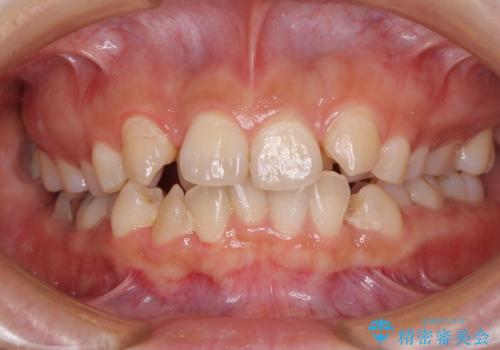

目立つ八重歯を治したい インビザラインによる矯正治療

見えないほど重なっている前歯 抜歯矯正でスッキリとした歯並びに